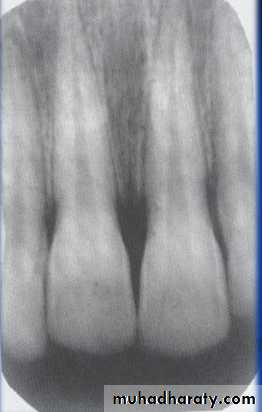

• Step 2: Assess the Periphery &Shape

• A:Well Defined borders:

Sharp margins:Punched out-sharp- eg.multiple myeloma.

Corticated margins: thin radiopaque line of reactive bone at the periphery of a lesion eg. cysts

principles of radiographic interpretation

Lateral periapical cyst-well defined corticated margin

Multiple myeloma -punched out lesion